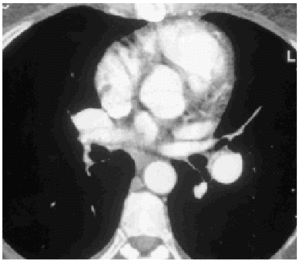

A lung ventilation-perfusion scan was requested (Figure 1) and showed multiple perfusion defects in both lungs in well-ventilated zones. The presence of pulmonary thromboemboli was therefore considered highly probable. Contrast-enhanced helical computed tomography (CT) confirmed dilation of the pulmonary artery and its branches as well as repletion defects in the right interlobar artery (Figure 2), which was reduced in diameter. Right heart catheterization revealed a systolic PAP of 65 mm Hg, a diastolic PAP of 30 mm Hg and a mean PAP of 45 mm Hg. After administering inhaled iloprost, a prostacyclin (prostaglandin I2) analogue, mean PAP fell 20%, with a resulting reduction in systemic blood pressure of the same amount. As none of the hospitals to which the patient could be referred carried out pulmonary thromboendarterectomy the patient continued to receive treatment with oral anticoagulants and inhaled iloprost.

Fig. 2. Helicoidal CT of the thorax showing reduced diameter of the right interlobar artery.